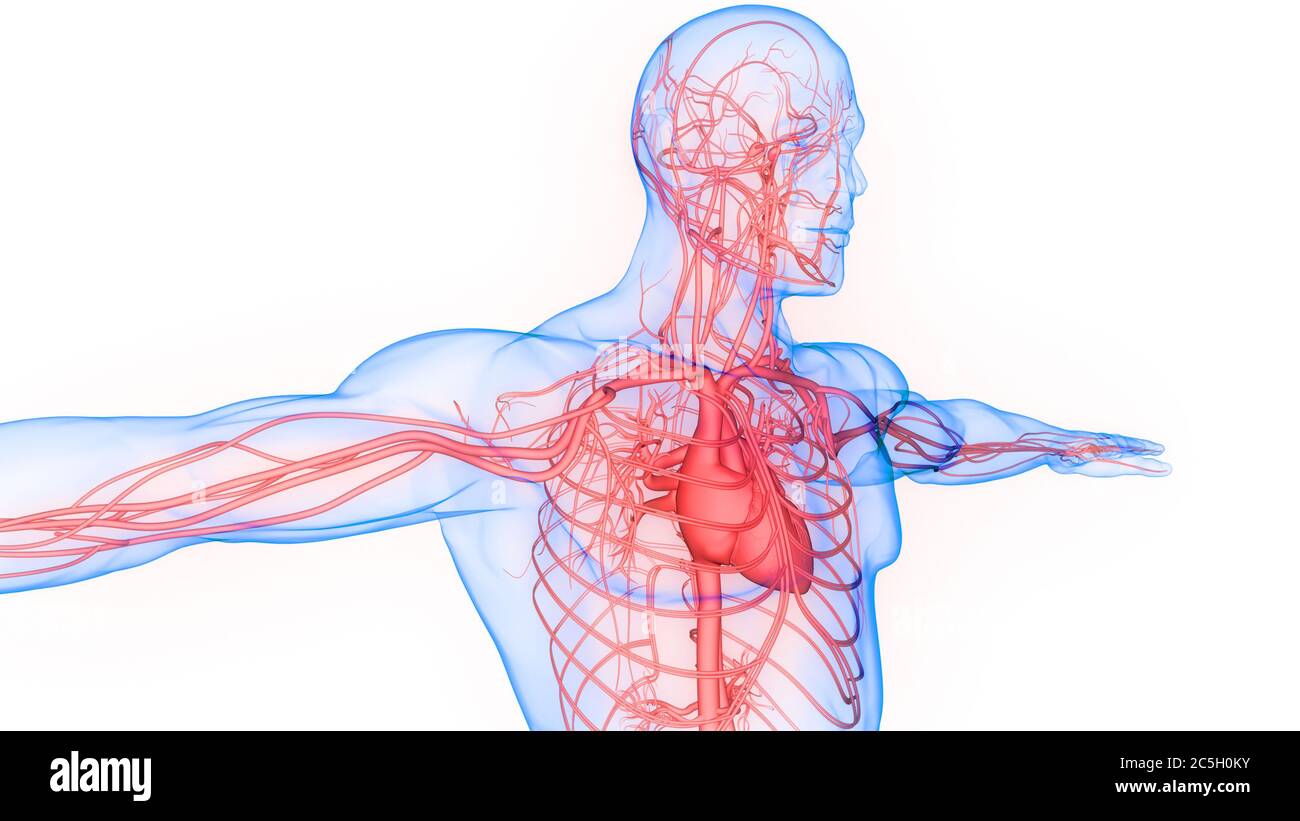

Анатомия человека: кровеносная система и её связь со скелетом